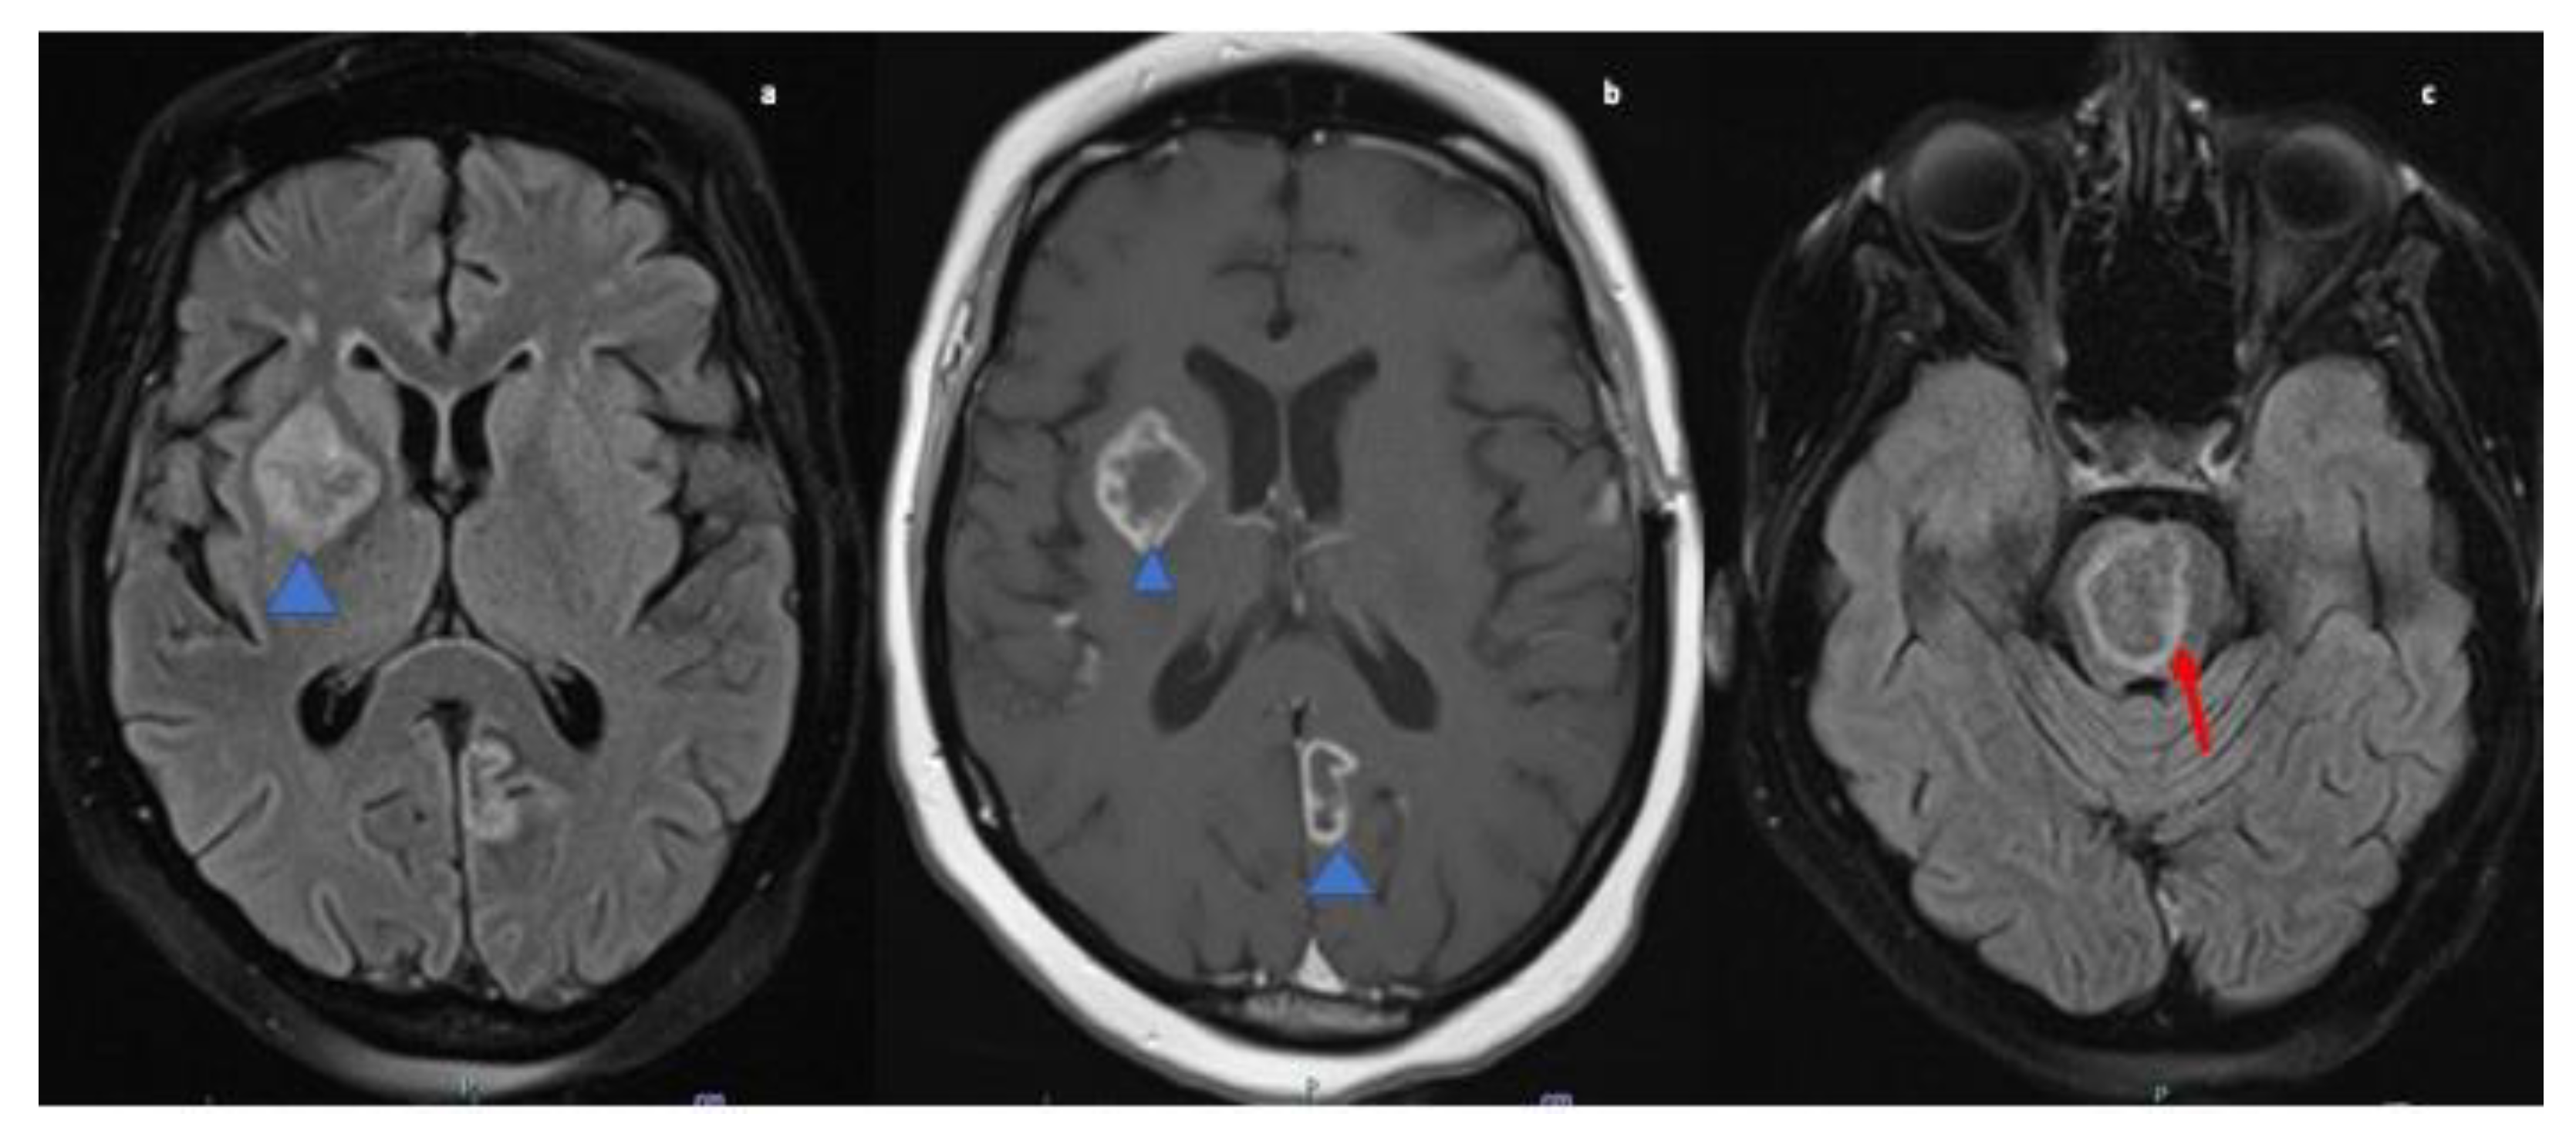

A 47-year-old African American female with past medical history of hypertension was transferred from an outside hospital after presenting with left sided upper and lower extremity weakness., MRI brain was performed which demonstrated multiple ring-enhancing lesions on post contrast T1 images, the largest within the right basal ganglia and the pons. There was also a smaller lesion in the left medial occipital lobe (refer Figure 4. The findings were concerning for possible demyelinating disease such as tumefactive multiple sclerosis, metastases or infection. A CT chest, abdomen, and pelvis revealed uterine masses likely representing uterine fibroids but otherwise no evidence of malignancy. Subsequently MRI of the pelvis was performed for further work up of the uterine masses which showed the large heterogeneous uterus was most likely due to degenerative fibroids and no suspicious uterine lesion was seen. Lumbar puncture was not performed due to concern for increased ICP. TTE was performed to rule out infective endocarditis and showed no evidence of valvular vegetations. Autoimmune and infectious serum panel were all negative.

Figure 4.

MRI Brain axial fluid-attenuated inversion recovery (FLAIR; (a)) & T1-weighted post contrast image (b) reveals hyperintense lesion in right gangliocapuslar region (blue arrowhead; (a)) with corresponding heterogenous peripheral ring enhancement, in addition to enhancement in the left paramedian occipital lobe (blue arrow head; (b)). FLAIR image (c) reveals circumscribed intra-axial parenchymal lesion in the pons (red arrow).

A brain biopsy was performed and final pathology showed necrotizing granulomas with associated calcifications consistent with NS. Biopsy stains for acid-fast and fungal (methenamine silver and PAS) organisms, with appropriate positive controls, were performed and were negative. A Congo red stain, with an appropriate positive control, was also performed and was negative. The patient was started on methylprednisolone 1 g daily for a total of five days. At the time of discharge the patient was switched to prednisone 60 mg daily for a total of 30 days and advised to follow up in the neurology clinic in four weeks after discharge. The patient reported an improvement in the left sided weakness on his follow-up visit. In addition to prednisone 60 mg daily, the patient was prescribed omeprazole 20 mg daily and advised to continue with home medications (refer Table 1).

MRI brain and orbits revealed an enhancing left cerebellar nodule with surrounding abnormal hyperintense signal on FLAIR extending to the cerebellar peduncle. Mass-like enhancement of the folia surrounding the nodule was also noted. MRI orbits showed bilateral smooth optic nerve sheath enhancement without abnormal signal within the optic nerves. There were also imaging findings concerning for papilledema with flattening of the posterior globes (refer Figure 5) and T2 images (not shown) also demonstrated intraocular protrusion of the optic nerve heads. These findings were most consistent with inflammatory processes such as sarcoid or possible leptomeningeal metastatic disease.

Figure 5.

MRI orbit axial T1-weighted fat-suppressed post contrast image (a) and coronal (b) images reveal enhancement of bilateral optic nerve sheaths (red arrow). MRI Brain axial fluid-attenuated inversion recovery (FLAIR) (c) image reveals ill-defined patchy parenchymal hyperintensity in the left cerebellar hemisphere extending to the cerebellar peduncle (blue arrowhead).

Non-specific MRI findings such as periventricular white matter lesions, meningeal enhancement, brain parenchymal lesions, dural mass lesions, and spinal cord involvement are commonly reported in NS [1,34,35]. However, ring-enhancing lesions, though reported rarely, may be the only presentation of NS [36,37]. Case four presented with increased intracranial pressure due to cerebral vasogenic edema and multiple ring-enhancing lesions adding neoplastic lesions, demyelinating diseases, contusions, and Wegner’s granulomatosis to the differential list. Such a case poses unique challenges in diagnosis as many of the differentials cannot be excluded immediately because of inability to perform LP in the presence of cerebral edema. However, whole-body imaging narrowed down the diagnosis of NS and it was confirmed by biopsy.

The presenting symptoms of case five were retro-orbital pain, blurring of vision progressively leading to complete diminution and fundoscopic examination revealing papilledema consistent with increased ICP. However, cerebellar and cervical leptomeningeal enhancement were also discovered on MRI, and the patient exhibited no symptoms from these lesions. Hence, it appears that in some cases of NS the imaging findings may not correlate entirely with the clinical presentation of the disease.